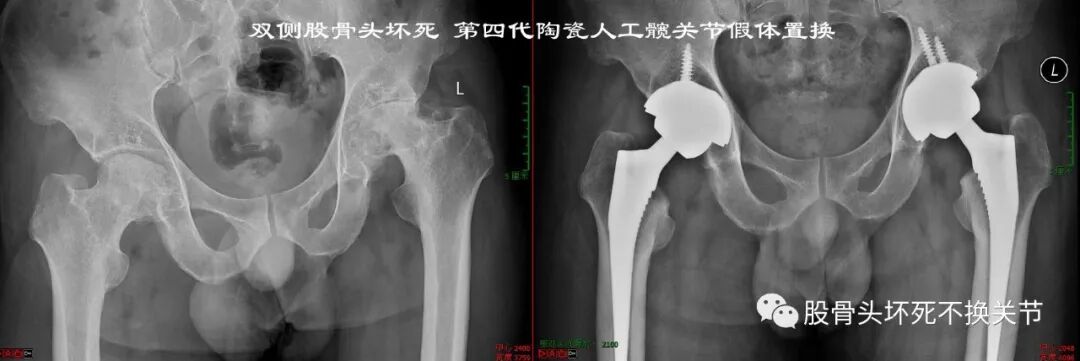

44岁,双侧全陶瓷关节置换

优点:

陶瓷材料的离子结构可以吸引带极性的液体,使之均匀地覆盖在陶瓷的表面,有利于形成流体薄膜润滑效果,减少假体之间的摩擦。

陶瓷材料非常坚硬, 其硬度仅次于金刚石, 远高于钴铬合金和钛合金等金属材料, 因此陶瓷制成的部件不易被划伤。

陶瓷为生物惰性材料,化学键稳定,组织学反应低,无腐蚀性,陶瓷颗粒对组织的刺激也较金属颗粒小;磨损时产生颗粒小,组织反应小,所以陶瓷关节可有效的减轻骨溶解。

一项多中心前瞻性随机研究显示,17年时的假体存留率,CoC为96.8%,而MoP 为91.3%(P=0.0046),CoC关节没有发现骨溶解,而MoP 关节骨溶解的发生率为17.6%。